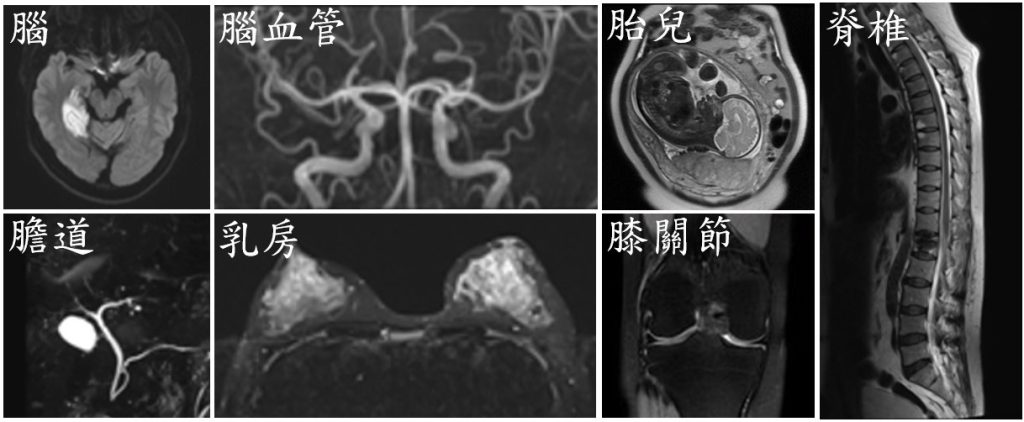

MRI 是利用強力磁場讓身體內氫原子(H) 產生共振,然後透過無線電波給予能量(射頻脈衝) 接收訊號,再由電腦建構出高解析影像。MRI在觀察軟組織方面特別清楚,例如腦神經、脊椎、關節、內臟與腫瘤,能提供豐富的細節,協助醫師做出準確判斷。

MRI應用廣泛,尤其適合以下狀況:

- 神經系統疾病:腦瘤、中風、多發性硬化症、脊髓壓迫損傷

- 運動傷害與關節問題:韌帶撕裂、半月軟骨損傷、椎間盤突出

- 腫瘤與癌症評估:乳癌、肝膽胰、攝護腺、婦科腫瘤等

- 其他:聽神經瘤、腦下垂體、心臟、胎兒MRI